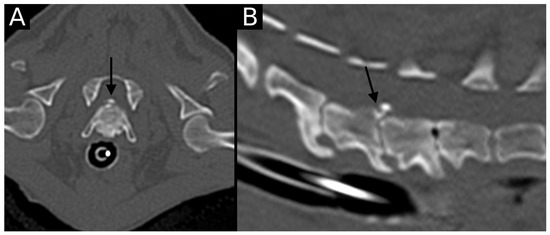

The junction between the endplates and intervertebral discs of the cervicothoracic junction (C6–C7, C7–T1 and T1–T2) were evaluated for the presence of alterations. When present, they were also graded and scored for EPJA, IVD herniation, spondylosis deformans, endplate sclerosis, articular process joint osteoarthrosis, and the presence of vertebral morphological abnormalities. The scoring system for endplate junction alterations and other spinal abnormalities was based on the proposed scoring by Tellegen et al. [13] for presumed EPJF at the lumbosacral spine. Endplate junction alterations were classified into four types (A, B, C, D): Type A involved presence of irregularity of the endplate margins without an obvious free fragment (Figure 1 and Figure 2); Type B involved avulsion evidenced by a thin rim of bone associated with a defect in the dorsal edge of the adjacent endplate (Figure 3); Type C included frank avulsion of a bony fragment (Figure 4) and Type D included presence of bony avulsion of both endplates. If EPJA was present, location (dorsal or ventral) and lateralization of the defect were also recorded. IVD herniation was graded from grades 0 to 3: grade 0 indicated no to mild (0–24%) herniation; grade 1 indicated mild to moderate (25–49%) herniation; grade 2 indicated moderate to marked (50–74%) herniation; grade 3 indicated marked herniation to complete obliteration (75–100%) of the vertebral canal by disc material. Spondylosis deformans was scored from grades 0 to 3: grade 0 indicated no enthesophytes; grade 1 indicated a small enthesophyte at the edge of the epiphysis that does not extend past the endplate; grade 2 indicated the presence of an enthesophyte that extends beyond the endplate but does not connect to the adjacent vertebra; and grade 3 indicated connecting enthesophytes from adjacent vertebrae forming a mineralized bridge. The other mentioned abnormalities (IVD mineralization, endplate sclerosis and articular process joint osteoarthrosis) were scored as present (1) or absent (0).

3.3. Other CT Abnormalities

All dogs (100%) with EPJA showed the presence of other vertebral abnormalities in the same intervertebral disc space. All endplates with EPJA had sclerosis, and other visualized abnormalities were spondylosis deformans (three cases, 27.3%), intervertebral disc mineralization (three cases, 27.3%), osteoarthrosis (one case, 9.1%), and intervertebral disc herniation (one case, 9.1%). In four cases (36.4%), two concurrent abnormalities were present (sclerosis and sclerosis and spondylosis, sclerosis and IVD mineralization, and sclerosis and osteoarthrosis), and the single patient (Chihuahua) with intervertebral disc herniation also had concurrent endplate sclerosis and spondylosis deformans. The other two dogs with spondylosis deformans were a Labrador and a crossbred. The other dogs with IVD mineralization were an American Staffordshire and a Labrador Retriever, and the only patient with articular process joint osteoarthrosis was a Golden Retriever. No dogs showed vacuum phenomena or morphological abnormalities in the intervertebral disc spaces affected by EPJA. The only positively correlated (p < 0.05) factors with EPJA were the presence of at least one vertebral abnormality and endplate sclerosis. However, when independently assessing the other factors, no positive correlation was observed with the presence of presumed EPJF (Table 2).

Figure 7. Transverse (A) and sagittal (B) reconstructions in the bone algorithm in the only dog with an intervertebral disc herniation. The C6–C7 intervertebral space is markedly narrowed, with the presence of moderate to marked spondylosis deformans, mild endplate sclerosis and mineralized herniated disc material. An irregularly defined contour defect is observed at the dorsal aspect of the caudal endplate of C6 (arrow). This was classified as EPJA Type A. The adjacent intervertebral disc spaces are also narrowed, with endplate sclerosis and spondylosis deformans. The vacuum phenomenon is also observed at C7–T1.